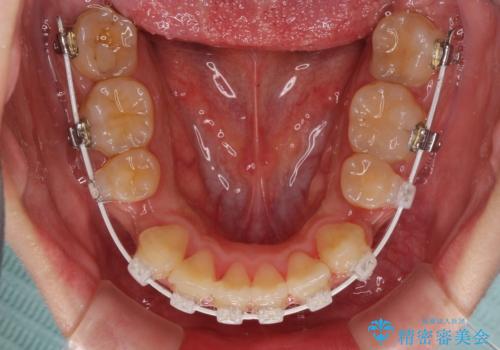

- 審美装置

- 1年11ヶ月

- 10-30回

口腔内の清掃性に問題があり、虫歯のリスクが極めて高かったため、短期で治療を終えることを最優先に治療を進めました。